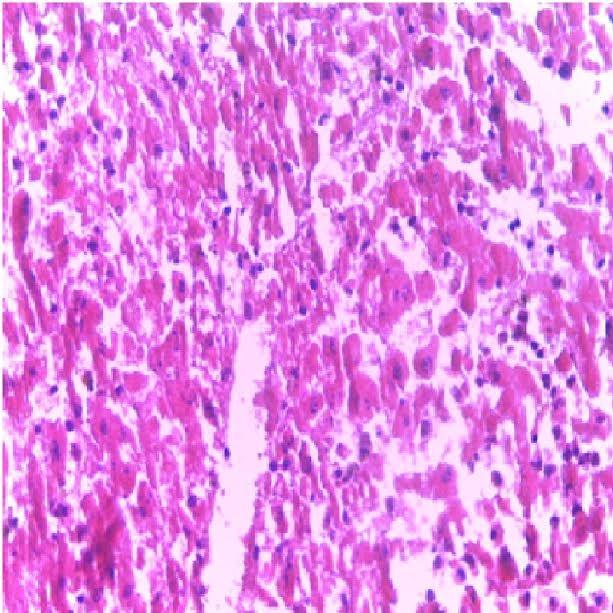

The therapeutic benefit derived from the clinical use of tramadol (TD) has been characterized by hepatotoxicity due to misuse and abuse. The implications of drug-induced hepatotoxicity include socio-economic burden which makes the search for remedy highly imperative. The present study investigated the protective effects of melatonin (MT) and n-acetylcysteine (NAC) on TD-induced hepatotoxicity in albino rats. Forty five adult rats used for this study were divided into nine groups of five rats each. The rats were pretreated with 10mg/kg/day of NAC, 10mg/kg/day of MT and combined doses of NAC and MT prior to the administration of 15 mg/kg/day of TD intraperitoneally for 7 days respectively. At the termination of drug administration, rats were weighed, sacrificed, and serum was extracted and evaluated for liver function parameters. The liver was harvested, weighed and evaluated for oxidative stress indices and liver enzymes. Alanine aminotransferase, alkaline phosphatase, aspartate aminotransferase, total bilirubin, conjugated bilirubin, and malondialdehyde levels were significantly (P<0.05) increased in rats administered with TD when compared to control. Furthermore, glutathione, superoxide dismutase and catalase levels were decreased significantly (P<0.05) in rats administered with TD when compared to control. The Liver of TD-treated rats showed necrosis of hepatocytes. However, the observed biochemical and liver histological alterations in TD-treated rats were attenuated in NAC and MT pretreated rats. Interestingly, pretreatment with combined doses of NAC and MT produced significant (P<0.05) effects on all evaluated parameters in comparison to their individual doses. Based on the findings in this study, melatonin and n- acetylcysteine could be used clinically as remedies for tramadol associated hepatotoxity.

曲马多(TD)临床使用所带来的治疗益处因误用和滥用而表现为肝毒性。药物性肝毒性的影响包括社会经济负担,这使得寻找补救措施迫在眉睫。本研究调查了褪黑素(MT)和N-乙酰半胱氨酸(NAC)对TD诱导的白化大鼠肝毒性的保护作用。本研究使用的45只成年大鼠分为9组,每组5只。在分别腹腔注射15mg/kg/天的TD共7天之前,大鼠分别用10mg/kg/天的NAC、10mg/kg/天的MT以及NAC和MT的联合剂量进行预处理。在药物给药结束时,对大鼠称重、处死,提取血清并评估肝功能参数。摘取肝脏,称重并评估氧化应激指标和肝酶。与对照组相比,给予TD的大鼠丙氨酸氨基转移酶、碱性磷酸酶、天冬氨酸氨基转移酶、总胆红素、结合胆红素和丙二醛水平显著(P<0.05)升高。此外,与对照组相比,给予TD的大鼠谷胱甘肽、超氧化物歧化酶和过氧化氢酶水平显著(P<0.05)降低。TD处理大鼠的肝脏显示肝细胞坏死。然而,在NAC和MT预处理的大鼠中,TD处理大鼠中观察到的生化和肝脏组织学改变有所减轻。有趣的是,与它们的单独剂量相比,NAC和MT联合剂量预处理对所有评估参数均产生显著(P<0.05)影响。基于本研究的结果,褪黑素和N-乙酰半胱氨酸可在临床上用作曲马多相关肝毒性的补救措施。